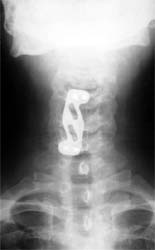

患者男性,30岁,腰3骨折,截瘫

CT显示腰3椎体爆裂,骨块凸入椎管压迫硬膜囊

施行后路椎管前方减压术及经椎弓根固定植骨术,彻底解除 脊髓前方的压迫及后凸畸形,截瘫部分恢复